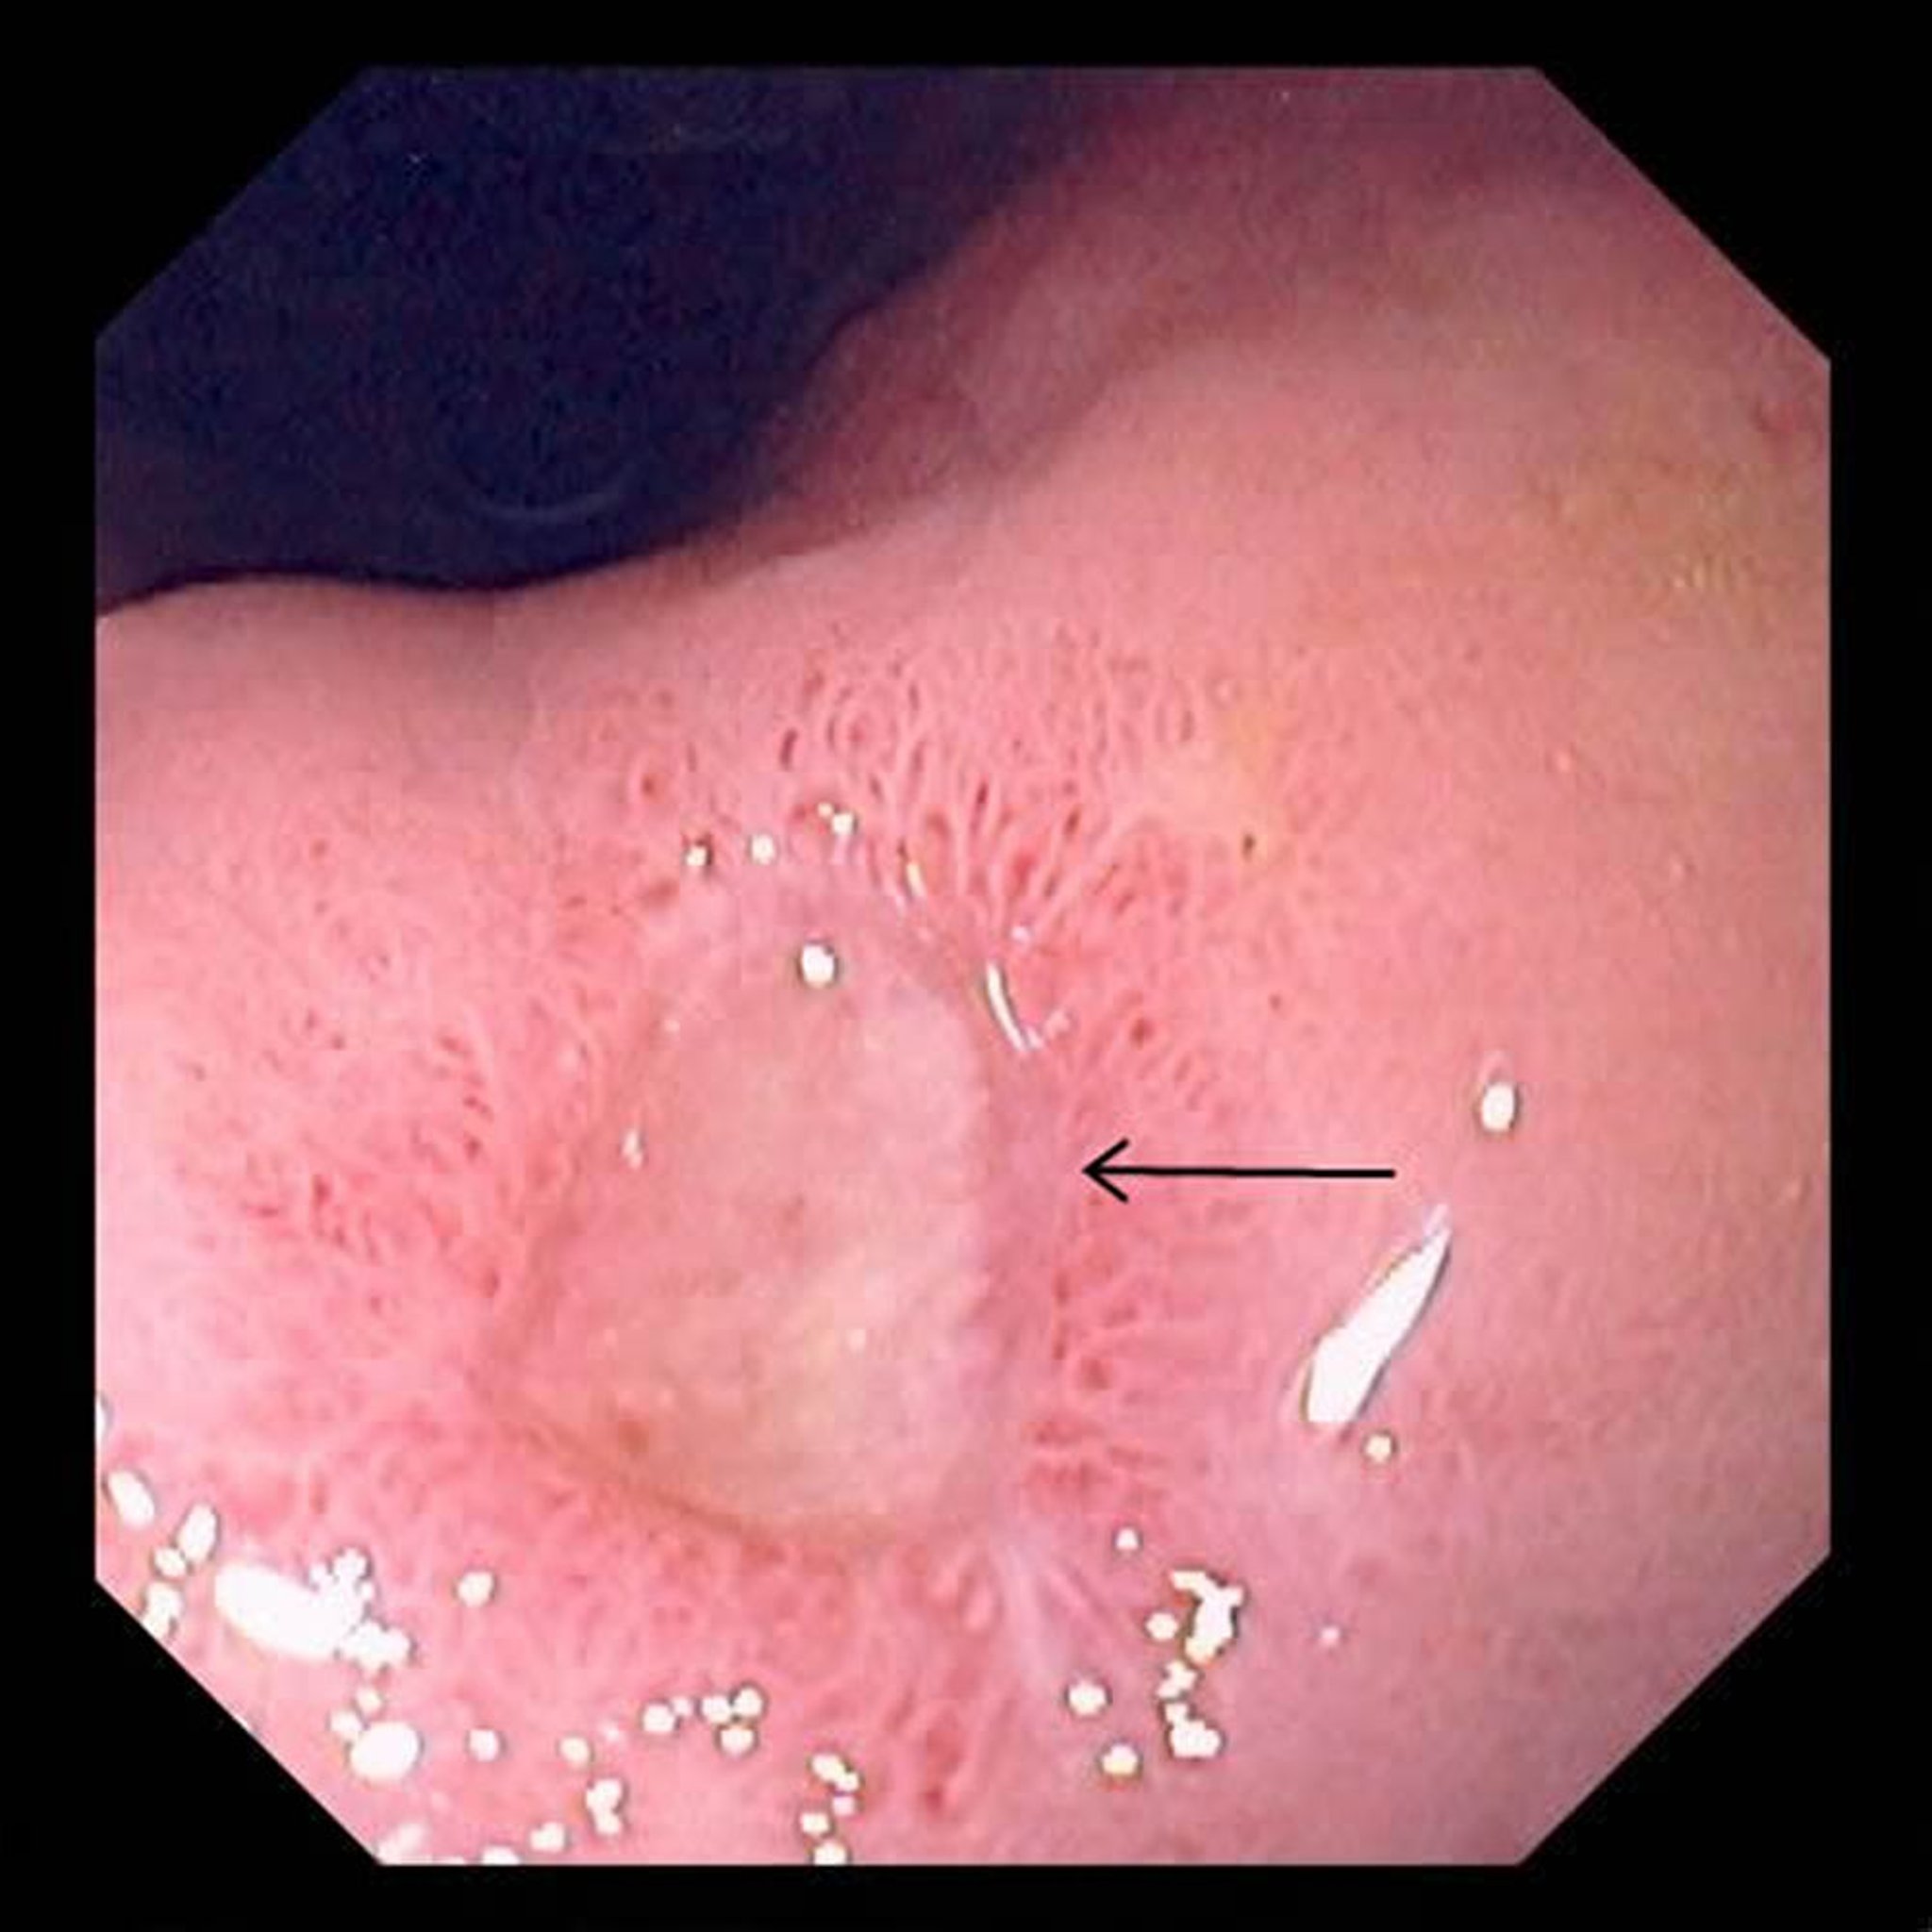

Esta fotografia exibe uma úlcera extensa (seta) no estômago.

Fotografia fornecida pelo Dr. David M. Martin.